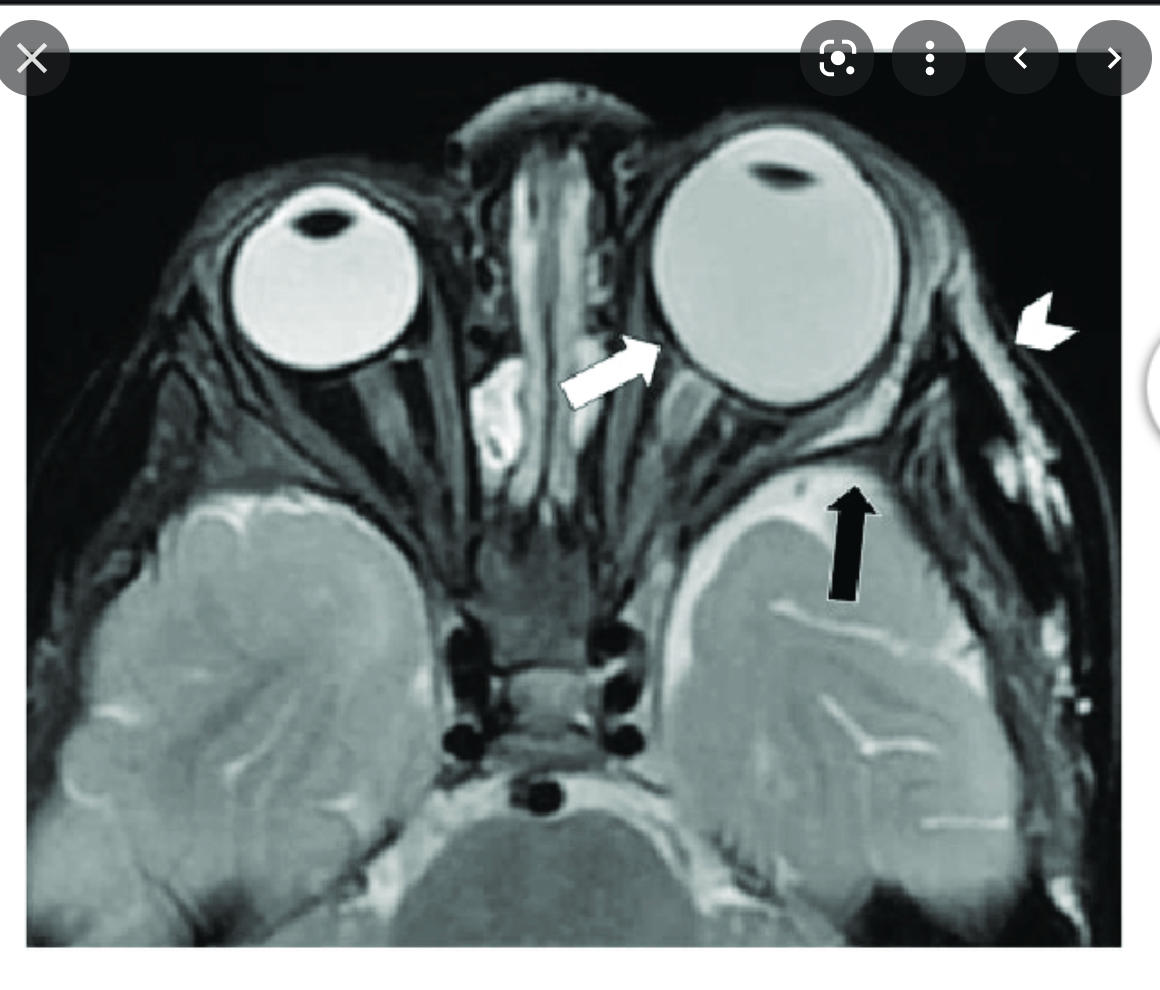

Buphthalmos

Buphthalmos: